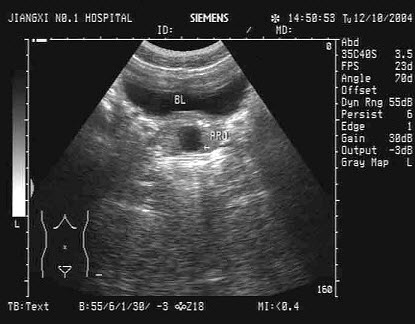

65、单项选择题

结合超声图像,该病例肾结石为哪一部位()

A.下极肾盏

B.中极肾盏

C.上极肾盏

D.肾门

E.肾乳头处